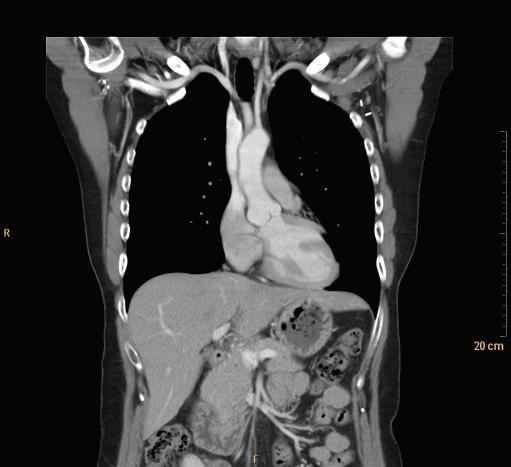

FIGURE 1-14 Coronal maximum intensity projection (MIP) of a chest CT.

FIGURE 1-18 Coronal CT of the chest.